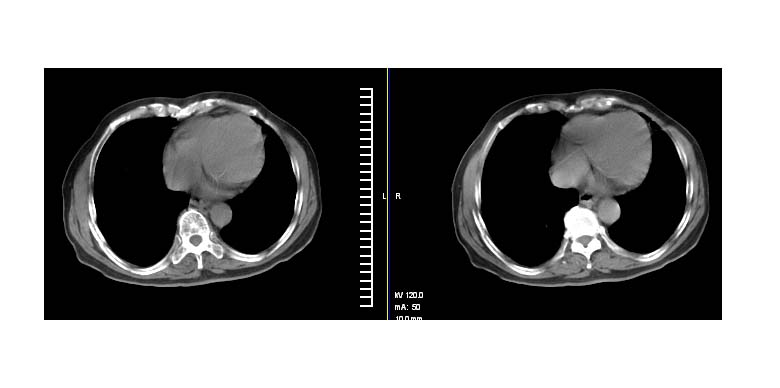

标题: CT11087:男性,82.咳嗽一周.抗炎治疗4-5天效果不明 [打印本页]

标题: CT11087:男性,82.咳嗽一周.抗炎治疗4-5天效果不明

左上肺周围型肺癌伴纵隔淋巴结转移

左肺上叶尖段周围型肺癌伴左肺门淋巴结转移。

左上肺实质性肿块,浅分叶 毛糙 胸膜凹陷征 纵隔淋巴结肿大——支持:左肺上叶周围型肺癌!

左上肺软组织肿块,有分叶,短毛刺,气管旁间隙见有肿大淋巴结,考虑左上周围型肺癌伴纵隔淋巴结转移。

左肺上叶前段肺癌并纵隔淋巴结肿大。